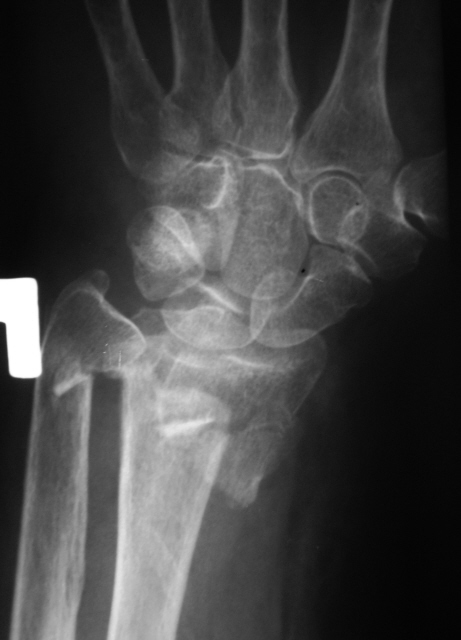

Катенёв Валенти... Дата публикации 23.04.2009, 18:55 Травма. Пациентка направлена на рентгенографию правого лучезапястного сустава. Проведена рентгенография, насколько это возможно, в стандартных проекциях. После репозиции отломков и наложения гипсовой повязки произведено рентген-контроль. Чт, 23/04/2009 - 19:21 #1 Dr.Mario Не на сайте Был на сайте: 11 лет 6 месяцев назад Зарегистрирован: 06.08.2008 - 08:44 Публикации: 920 плохо, очень плохо. Let me see... radiographia.ru Чт, 23/04/2009 - 20:48 #2 Vega Не на сайте Был на сайте: 4 месяцев 3 недели назад Зарегистрирован: 22.01.2009 - 19:16 Публикации: 1087 Да, нужно оперировать

плохо, очень плохо.

Да, нужно оперировать